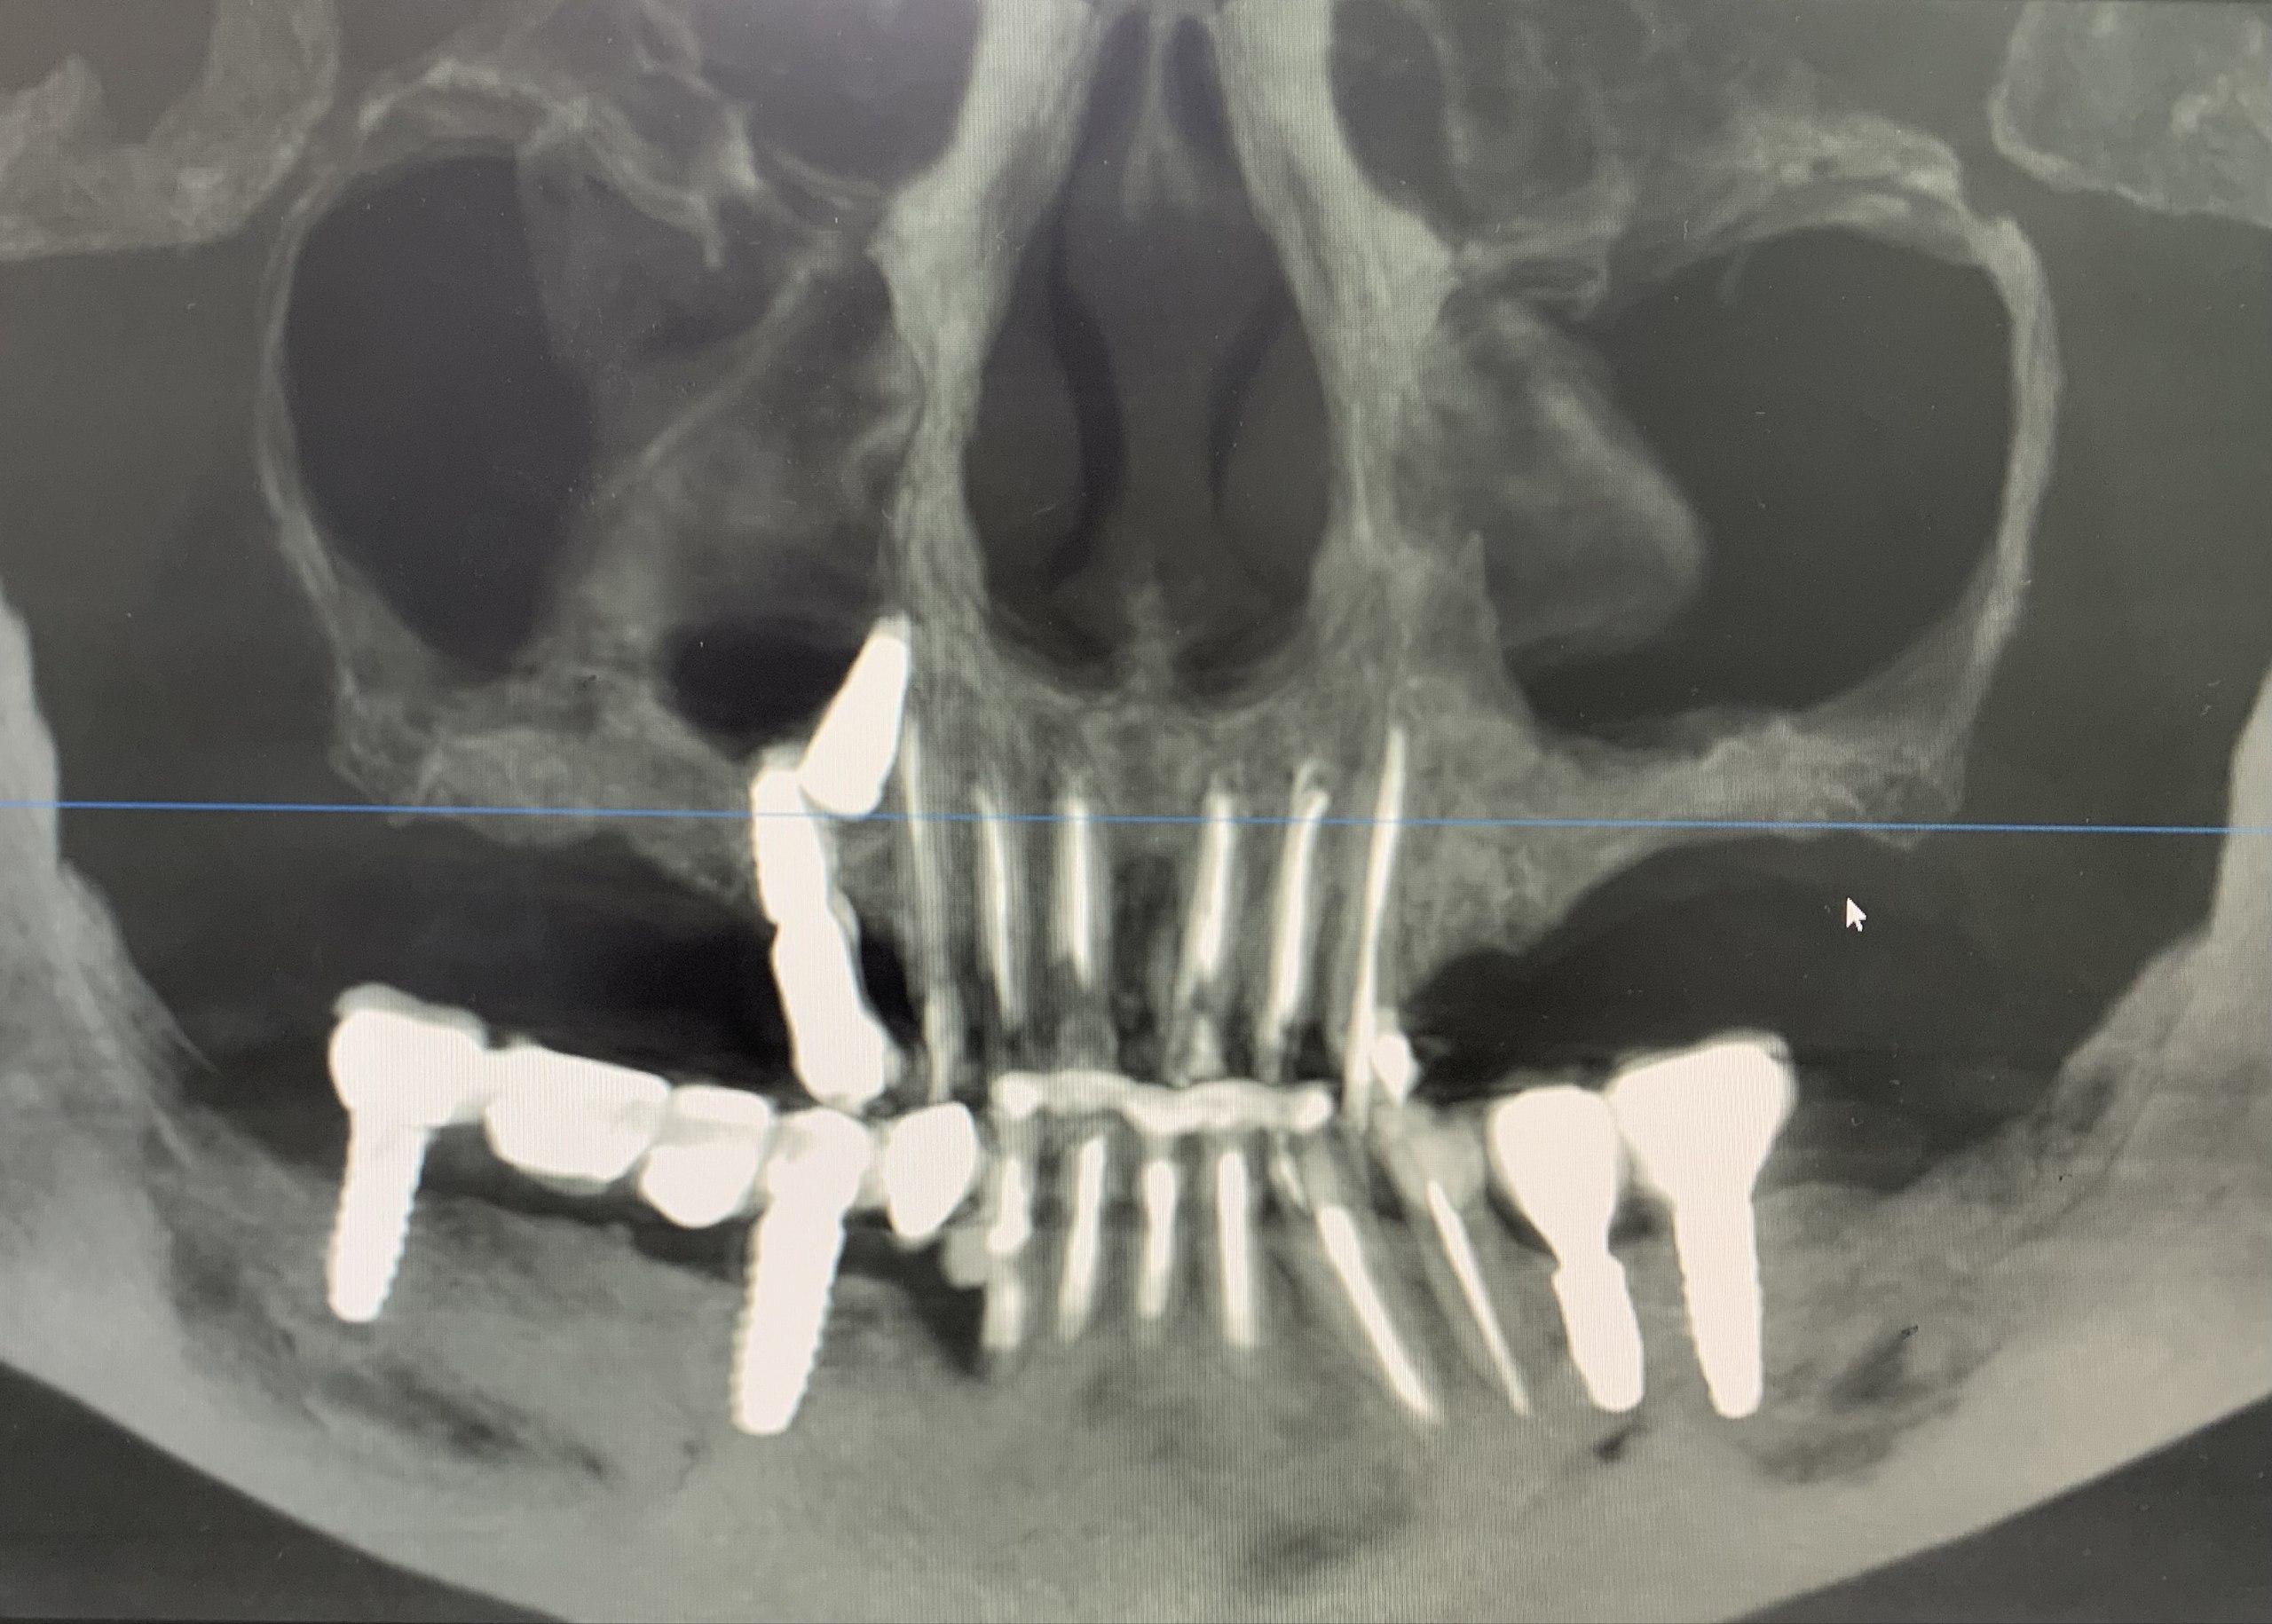

- На рентген исследовании обнаружен дезинтегрированный дентальный имплант расположенный в правой верхнечелюстной пазухе. Без следов локального воспаления и жалоб со стороны пациентки.

- Ортопантомограмма (ОПТГ).

- Конусно-лучевая компьютерная томография (КЛКТ).

- Гомогенная обтурация корневых каналов зубов (13,12,11,21,22,23). Периапикальные ткани и периодонтальные щели без видимых патологий.

- На ОПТГ: кариес корня зуба 32, требующий удаления.